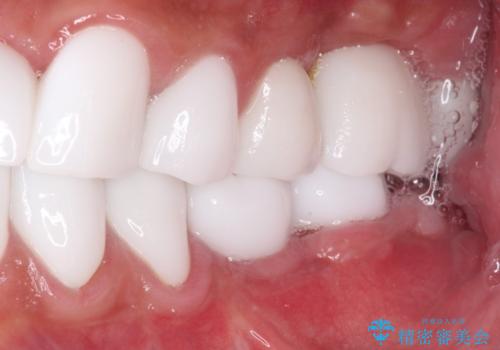

本来、あまりにも不自然な歯となるため、フルジルコニアクラウンを前歯に使用することは、咬合力が強すぎる場合を除き、ほとんどありません。

それでも、色調、形態ともに不自然なくらい真っ白な歯をご希望でしたので、患者様には大変満足していただきました。